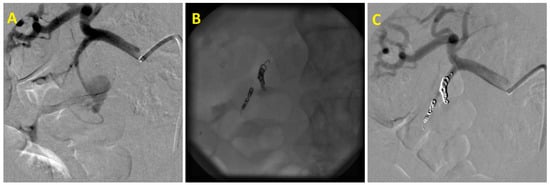

The median time interval between initial clinical manifestations and angiography was 5.5 days (14 h to 22 days). Pathological angiographic findings were confirmed in 24 out of 27 patients (88%). Active bleeding was identified in nine cases, pseudoaneurysms in seven patients (Figure 1), tumor enhancement was found four times, and pathological hypervascularization in the ulcer area was observed in two cases. Both arterioportal fistula and pseudoaneurysm with arteriovenous fistula in the liver were found once each. In three cases, it was not possible to angiographically identify the source of hemorrhage. Despite negative angiographic findings, two of these patients also underwent empirical embolization of the gastroduodenal artery, with continued bleeding from the duodenal ulcer, which was initially treated endoscopically. In total, embolization was performed in 26 patients (96%). The etiology of the hemorrhage, treated arteries, and used embolic materials are shown in Table 2.

Figure 1. Embolization of superior anterior pancreaticoduodenal artery pseudoaneurysm: (A)—Superior anterior pancreaticoduodenal artery pseudoaneurysm after pancreatic pseudocyst endoscopic treatment. (B)—Embolic agent–coils. (C)—Final angiogram confirming pseudoaneurysm occlusion.